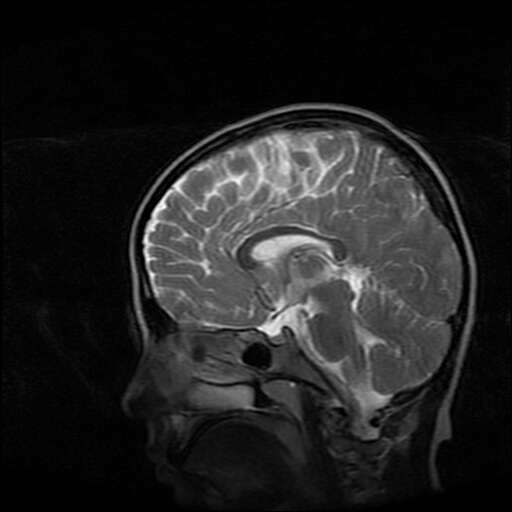

女,7岁,三岁才说话、走路。现智力尚可,走路不稳。临床怀疑大脑发育不全。

考虑胼胝体发育不全,髓鞘形成不良。

支持考虑胼胝体发育不全,髓鞘形成不良。

脑裂畸形伴灰质异位

侧脑室周围白质数量减少,侧脑室不对称性扩大,左侧侧脑室后角呈方形改变,脑沟加深,结合临床考虑脑室周围白质软化症(pvl)。期待结果!

只看出灰质异位